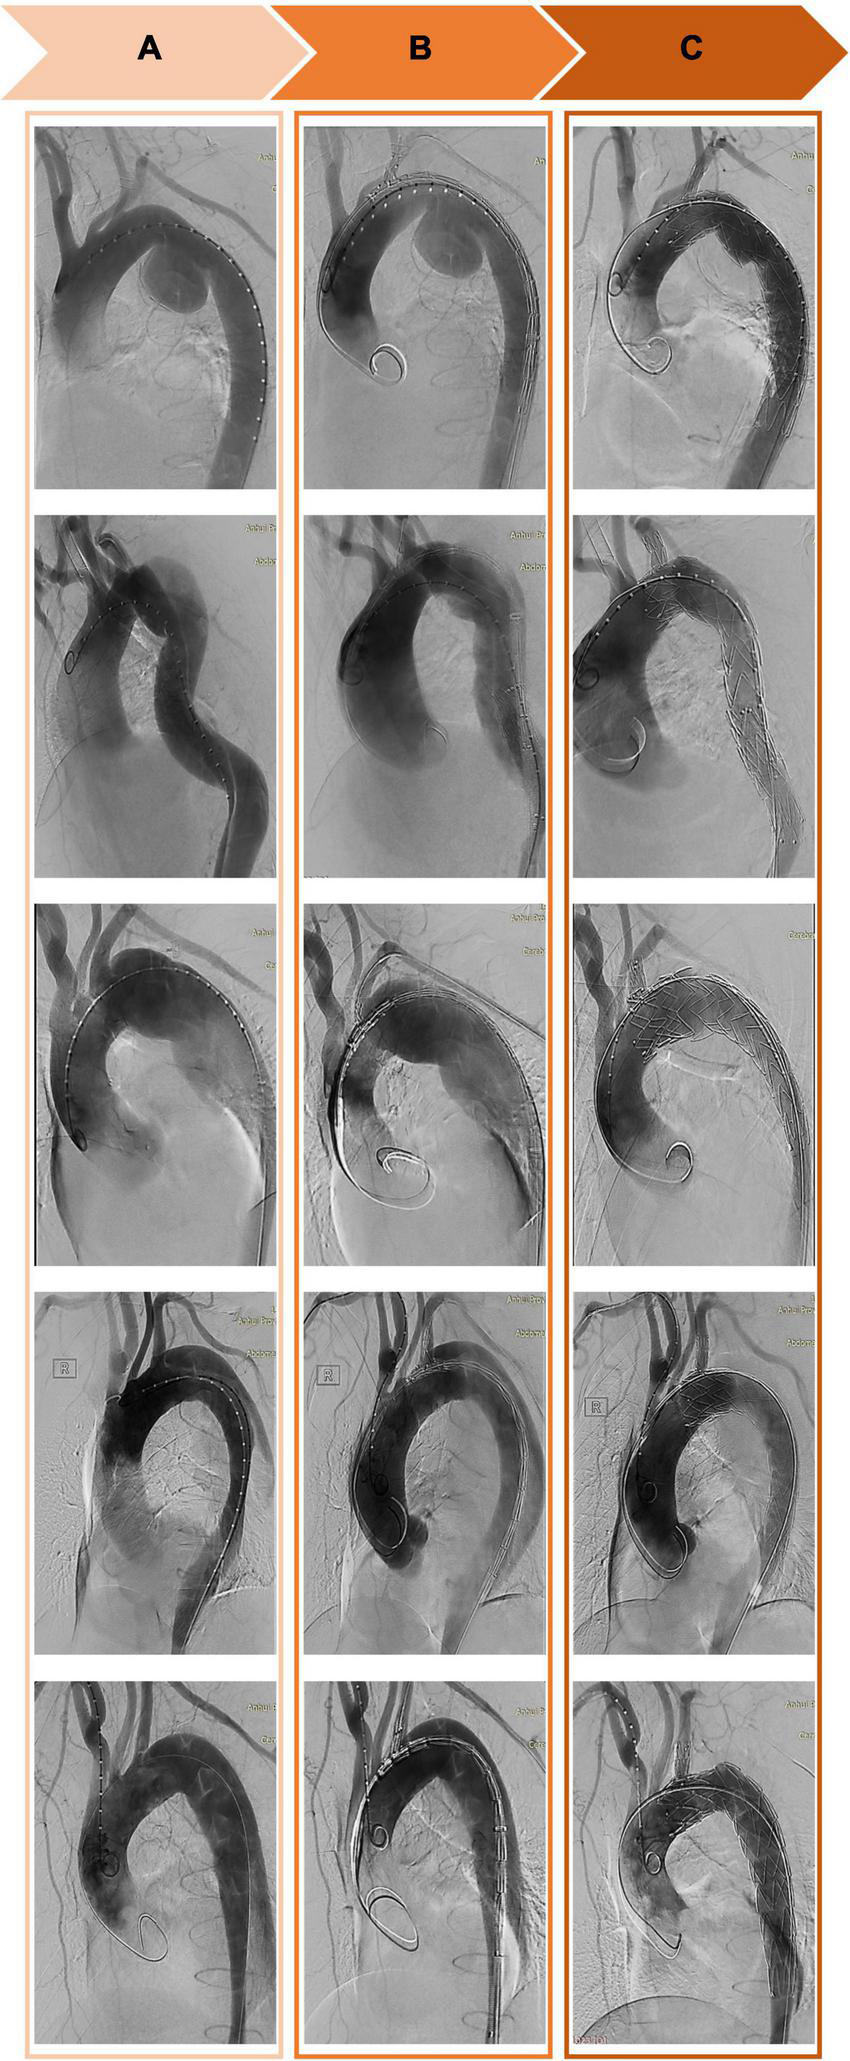

FIGURE 3

Computed tomography angiography of the thoracic aorta before (A), during (B), and after (C) implantation of a Castor single-branch stent graft.